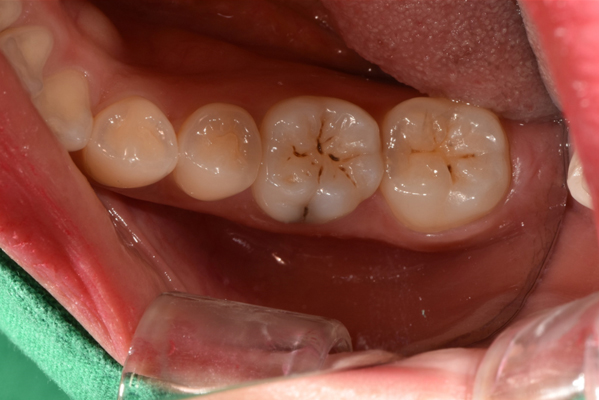

충치(치아우식증)로 인해 치아 조직의 손상이 있을 경우

대개 잘 보이지 않는

한두개의 점 모양

급격한 온도차에

의한 통증 발생